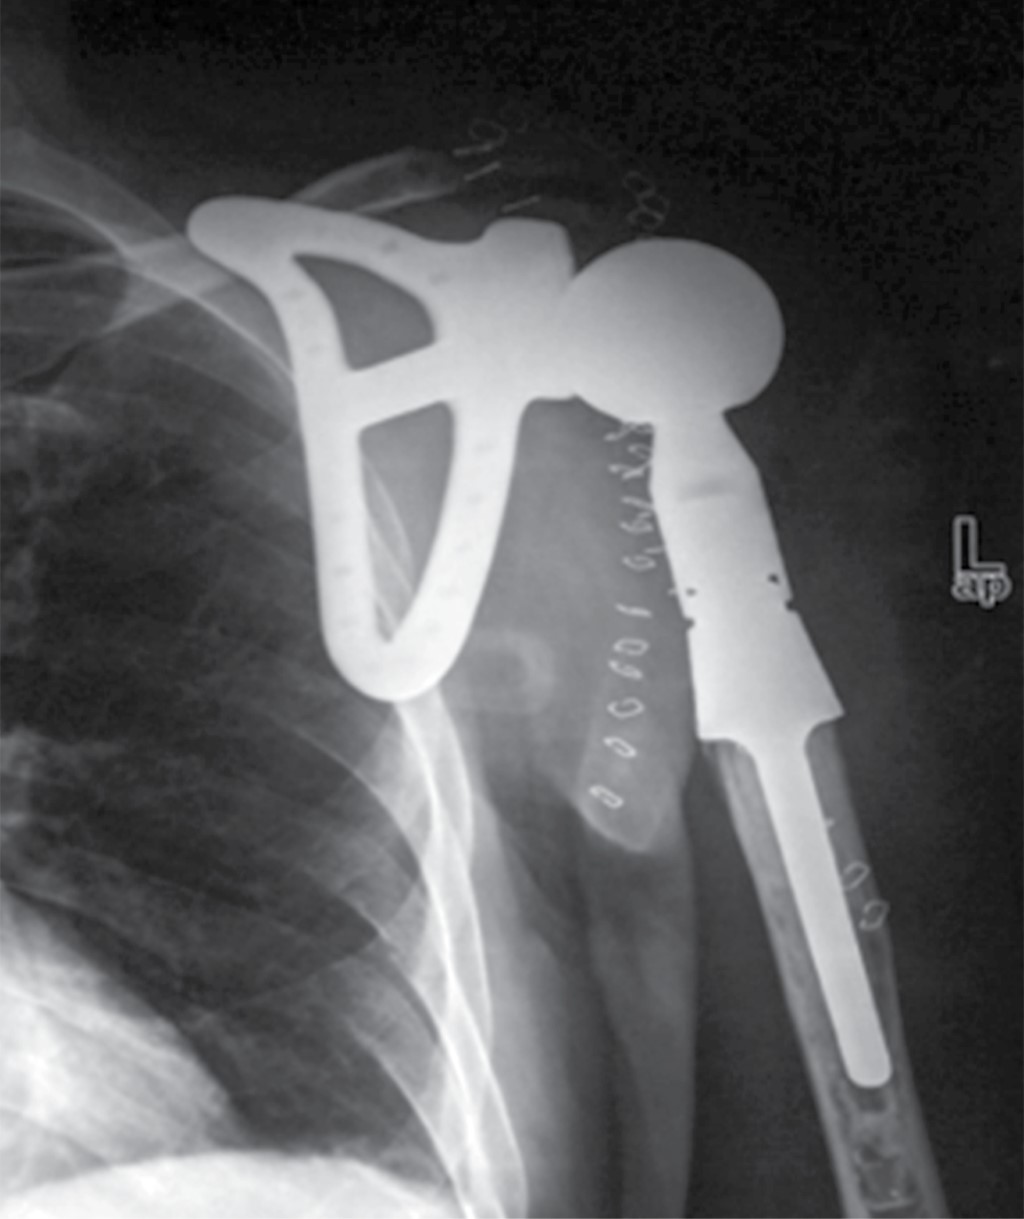

La incidencia del caso es 2-5:1'000,000, por lo que representa una rareza diagnóstica. En estudios donde se reporta el uso de la técnica de Tikhoff-Linberg tipo 410,11 se utilizan prótesis de escápula y/o húmero (Figura 7), en este caso se realizó una variable quirúrgica sin el uso de prótesis, por lo que se procedió a "anclar" el húmero de la clavícula residual por medio de sutura de poliéster (Figura 3), técnica de la que, a pesar de ser descrita por Linberg,8,11 no existen casos publicados sobre su uso. Se presenta radiografía posterior al procedimiento (Figura 8).

Figura 7

Figura 8